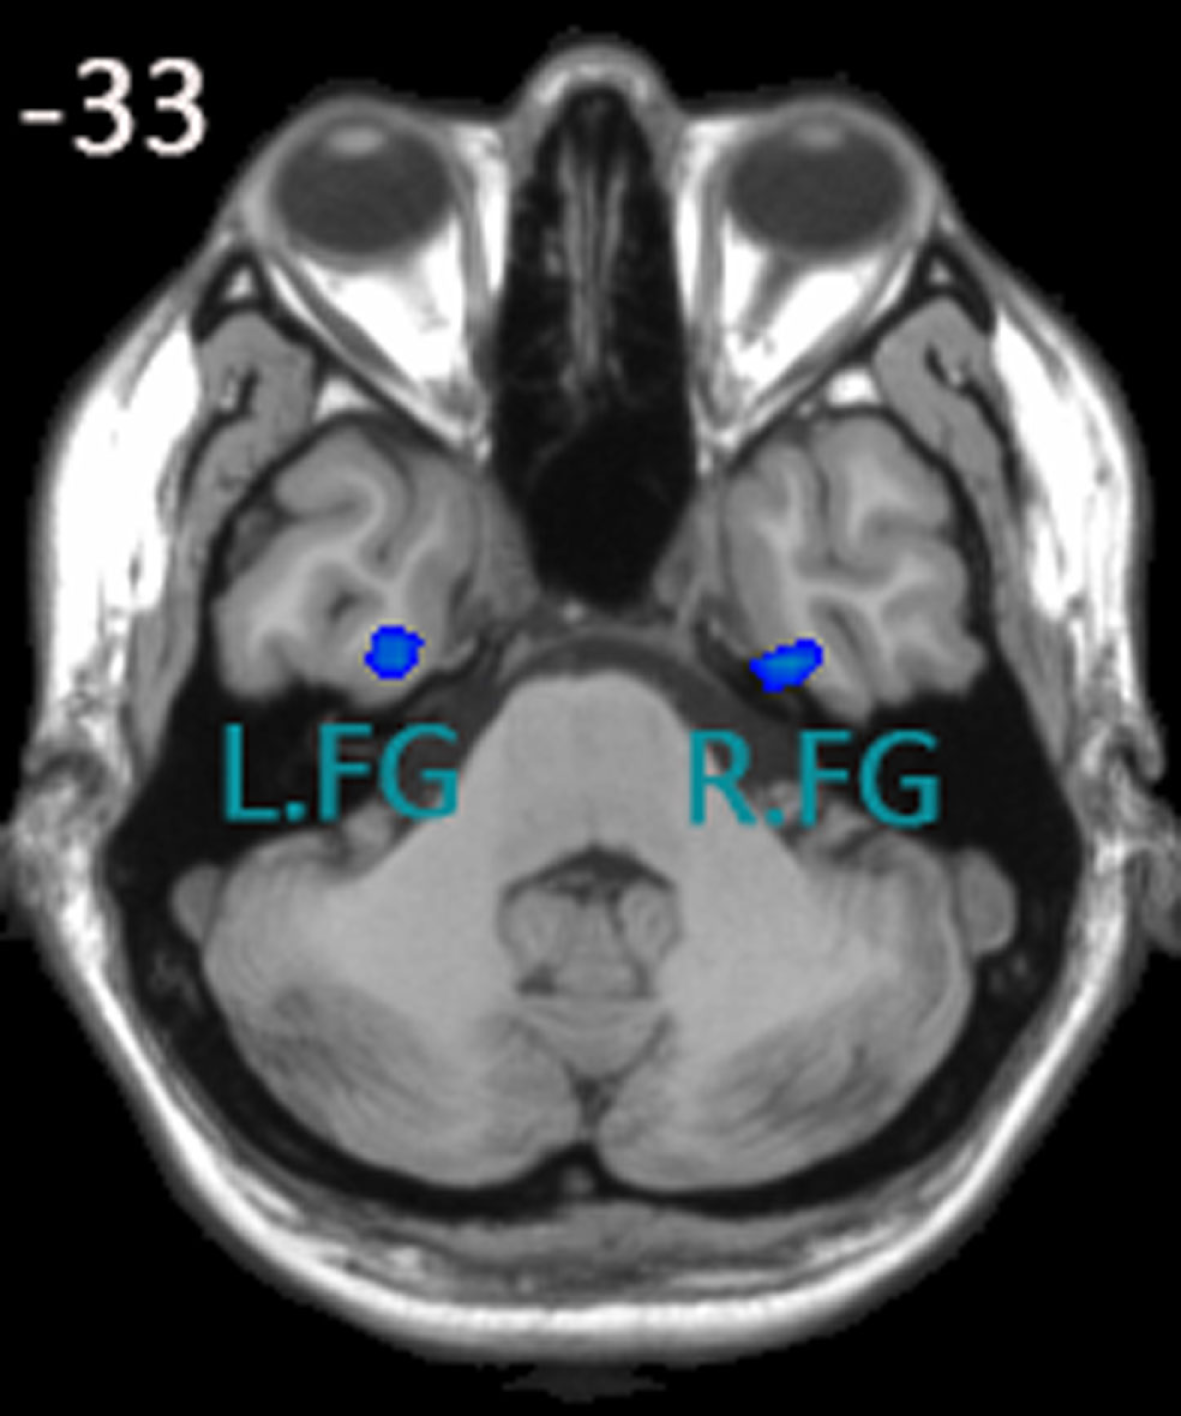

Using amplitude of the low-frequency fluctuation analysis to define seed regions

Yu-Feng et al. (2007) reported that amplitude of low-frequency (0.01–0.08 Hz) fluctuation (ALFF) is able to reflect the baseline brain function and could be used as a biomarker to assess spontaneous brain activity. Several studies employed it to measure the alterations in baseline brain activity for both healthy subjects (Zuo et al., 2010) and subjects with pathological conditions (Liu et al., 2012). Thus, we conducted the ALFF analysis using REST software to define the seed regions. The calculation procedure was similar as Yu-Feng et al. (2007)’s study. Subsequently, a voxel-wise two-sample t-test was carried out to compare the mALFF differences between the control group and aMCI group using REST 1.8 software. As was expected, one of the brain regions showing a significant difference between ALFF values was the FG (P < 0.05, false discovery rate corrected). We chose the left and right fusiform gyri as our seed regions (left FG volume: 1836 mm3, right FG volume: 2403 mm3), for more details, see Figure 1. Each seed region was re-sampled to obtain a new seed region image with the same spatial resolution as the preprocessed fMRI images using the 0 interpolation approach. Following this step, we carried out binarized transformation for each seed region to refrain the non-zero value.

Figure 1

Seed regions of the left FG and right FG; (1) x, y, z coordinates of primary peak locations in the space of MNI of the left FG are −28, −9, −38; t = −2.731; volume: 1836 mm3. (2) x, y, z coordinates of primary peak locations in the space of MNI of the right FG are 32, −10, −38; t = −2.935;volume: 2403 mm3.